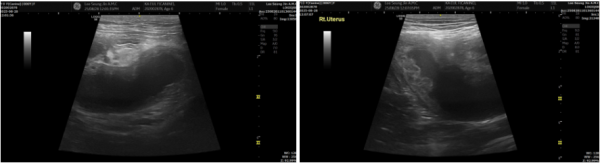

└양측 자궁각의 뚜렷한 확장, 자궁벽의 낭종성 변화가 확인되었습니다.

하복부 영상 스캔 시 뚜렷한 통증 반응이 있었고,

초음파 검사에서는 자궁 안에 농성삼출물이 가득 차

자궁이 크게 팽창된 자궁축농증이 확인되었습니다.

이 소견은 대형견 자궁축농증에서도 흔히 보이는 형태로,

농성삼출물이 자궁 밖으로 새어나간 흔적까지 보여

부분적인 복막염이 동반된 상황이었습니다.